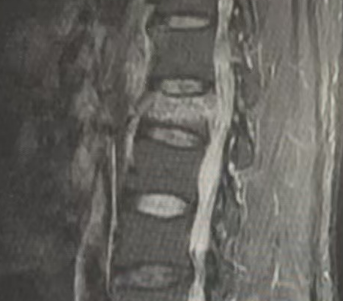

脊柱骨科开放床位30床。运用中医特色保守治疗颈、肩、腰腿痛疾病,西医手术治疗脊柱退行性疾病(颈椎病、椎间盘突出症、椎管狭窄症、脊椎滑脱),创伤性脊柱损伤及脊髓损伤,脊柱结核、肿瘤,脊柱侧弯等,尤其是脊柱微创治疗处于全省领先地位,椎间孔镜手术、OLIF手术及MIS-TLIF手术是我科优势技术,手术量在全省领先,并在全省率先划分为颈胸与腰椎两个发展方向。

1.退行性脊柱病(颈椎病、椎间盘突出症、椎管狭窄症、脊柱滑脱);